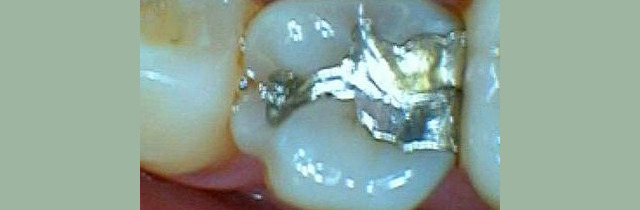

Restorative Dentistry

Restorative dentistry services focus on repairing teeth damaged to cavities, tooth decay, or trauma. From our beginning, it has been our goal to help our patients restore strength and structure to their smiles. We are committed to helping your smile stay beautiful and healthy for a lifetime. We incorporate the latest dental technology to ensure you receive the most advanced care. Our restorative services include:

Crowns

Composite Fillings